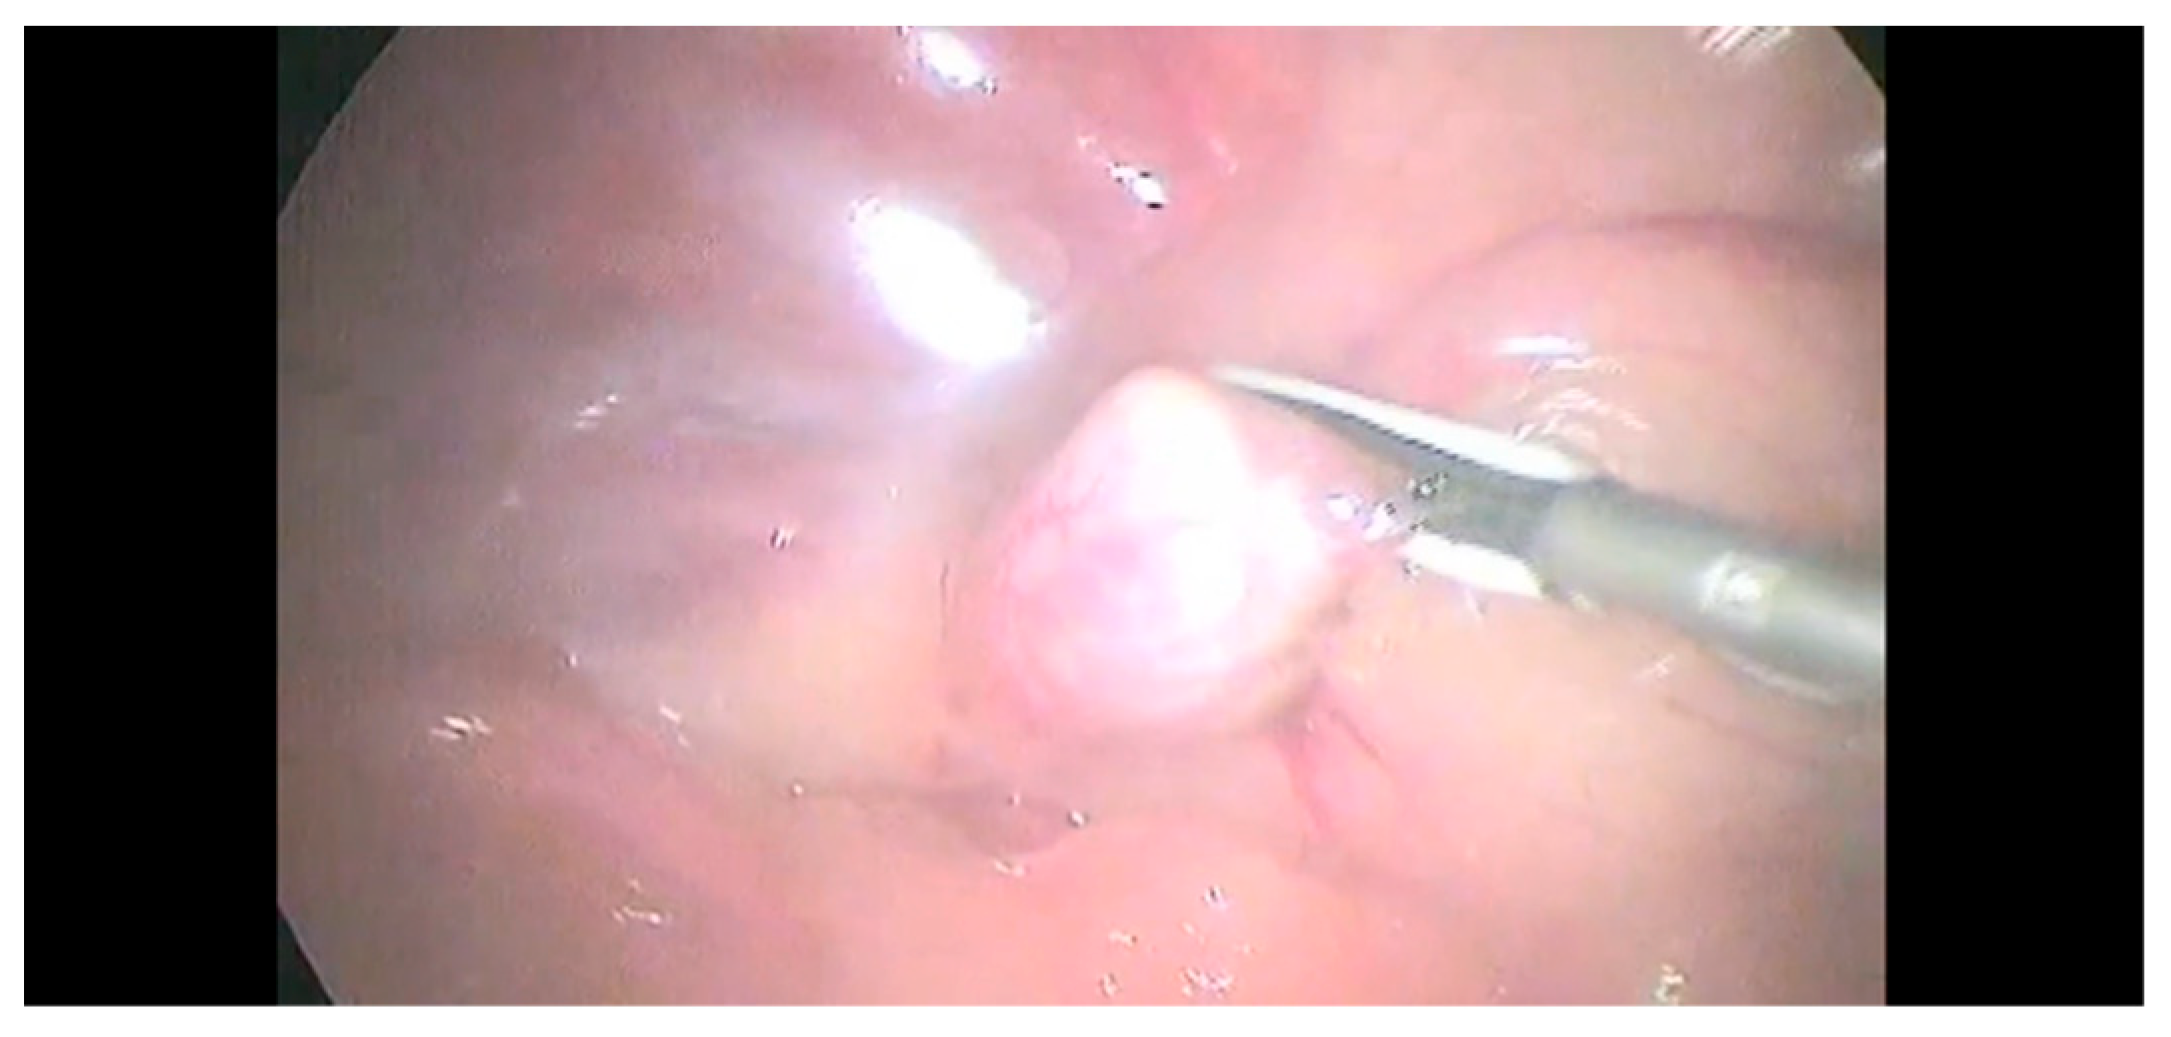

2.2. Surgical Procedure